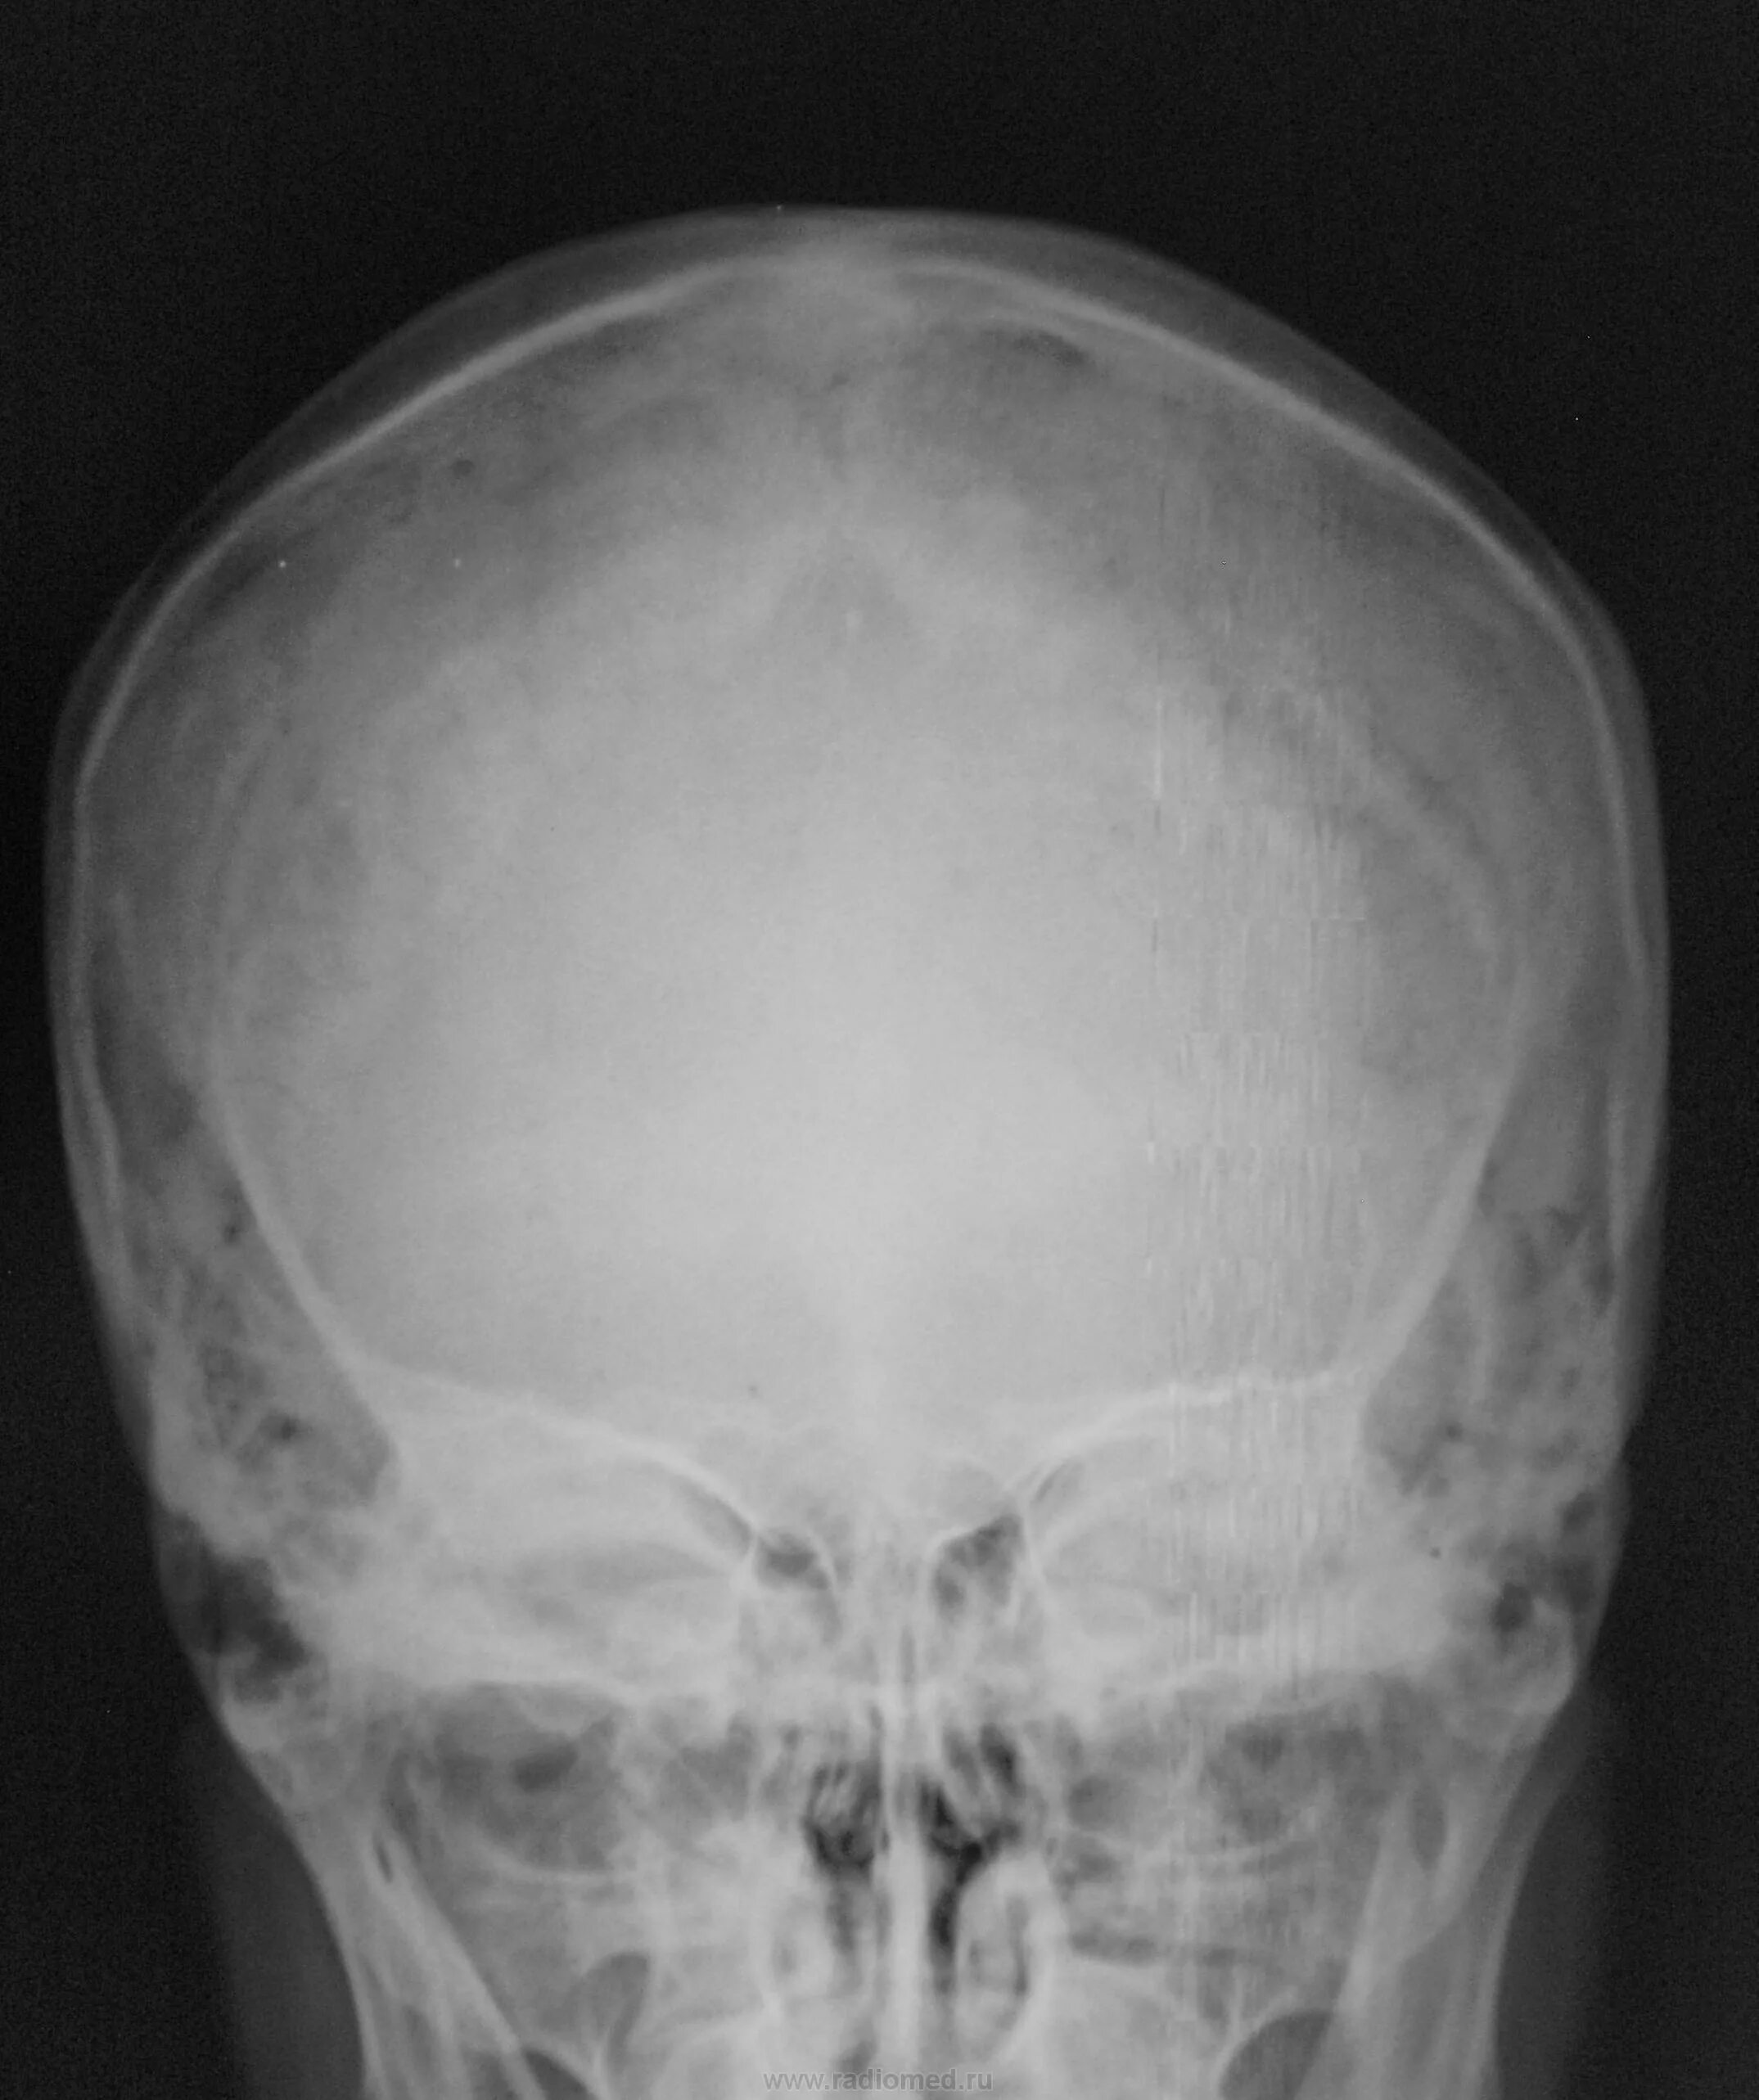

Снимок черепа в прямой проекции